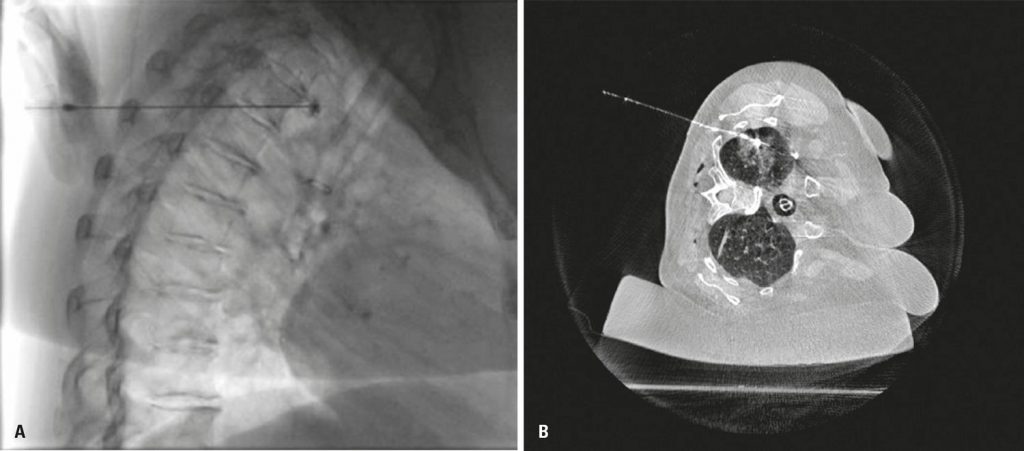

Lung nodule localization in hybrid room before minimally invasive thoracic surgery: series of 20 cases and literature review

To describe an experience in the preoperative localization of small pulmonary nodules and ground-glass lesions to guide minimally invasive thoracic surgery; in addition, a literature review was conducted, including the main advantages and disadvantages of the different agents used, and site marking in a hybrid operating room.

A retrospective search was conducted in a Interventional Radiology Department database, between March 2015 and May 2019, to identify patients undergoing preoperative percutaneous marking of lung injuries measuring up to 25mm.

A total of 20 patients were included and submitted to descriptive analysis. All patients were marked in a hybrid room, at the same surgical-anesthetic time. Most often used markers were guidewire, Lipiodol® and microcoils. Despite one case of coil displacement, two cases of pneumothorax, and one case of hypotension after marking, all lesions were identified and resected accordingly from all patients.

Preoperative percutaneous localization of lung injuries in hybrid room is an effective and a safe technique, which can have decisive impact on surgical resection. The choice of marker and of the operating room scenario should be based on availability and experience of service. Multidisciplinary discussions with surgical teams, pathologists, and interventional radiologists are crucial to improve outcome of patients.